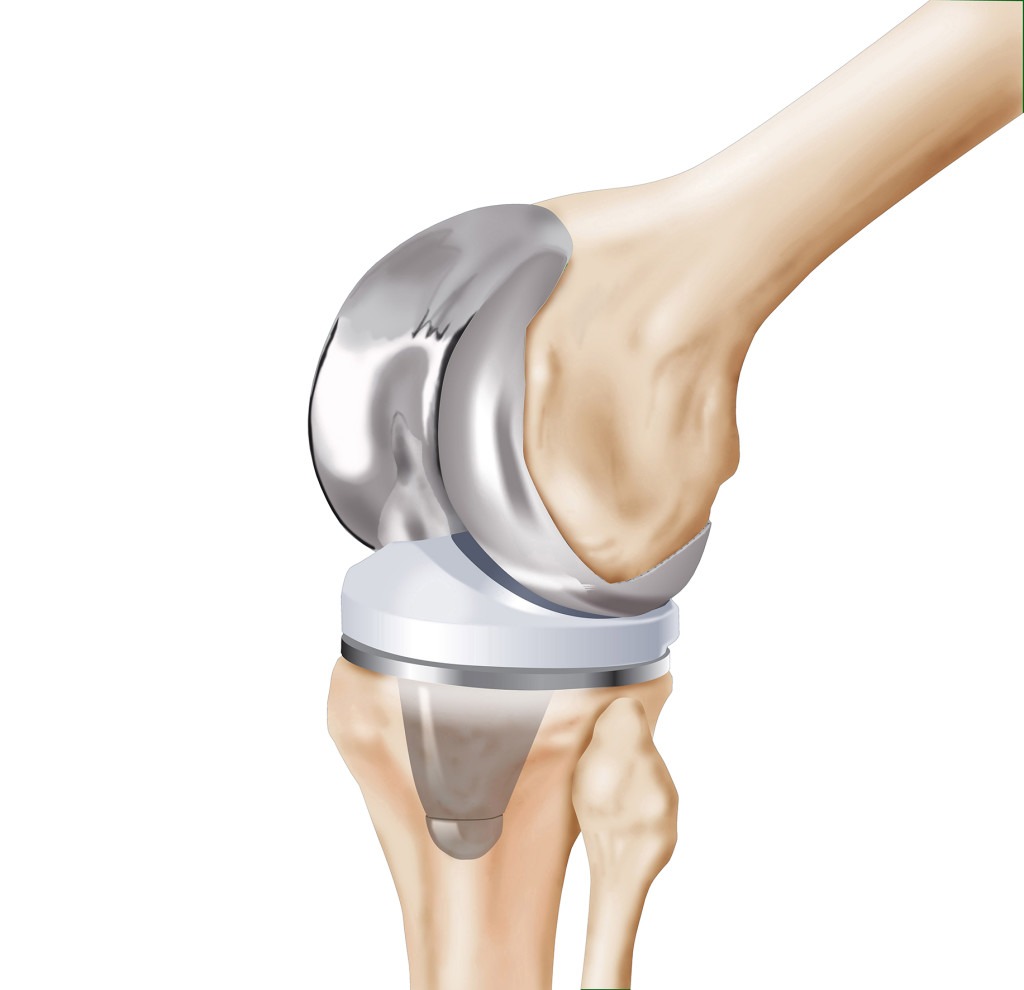

Total Diz Protezi

Devamı